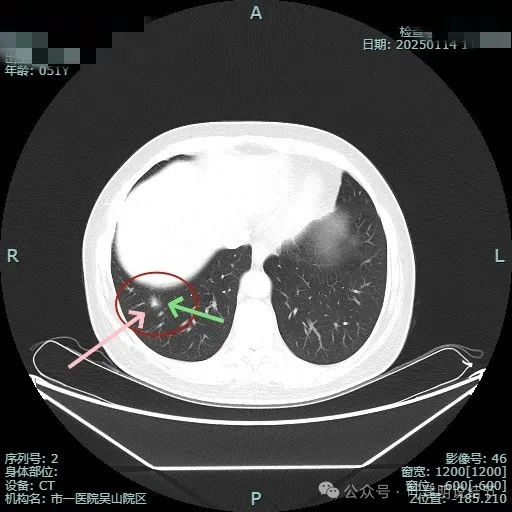

毛刺更明显,灶内密度不均,混合密度,表面不平。

灶内密度显杂乱,表面不平。

靶重建显示边缘细毛刺、外围磨玻璃密度,中间实性成分明显,表面不平有浅分叶。

中间实性成分感觉边缘较清,缺乏收缩力,外围的磨玻璃成分整体轮廓较清,边缘有细毛刺征。